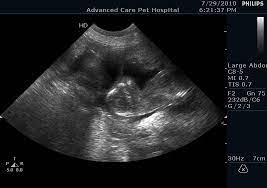

ULTRASOUND

Date | 12-06-2022 | Radiologist | Name of radiologist |

Description Lorem Ipsum is simply dummy text of the printing and typesetting industry. Lorem Ipsum has been the industry's stan |

Observation Lorem Ipsum is simply dummy text of the printing and typesetting industry. Lorem Ipsum has been the industry's stan |